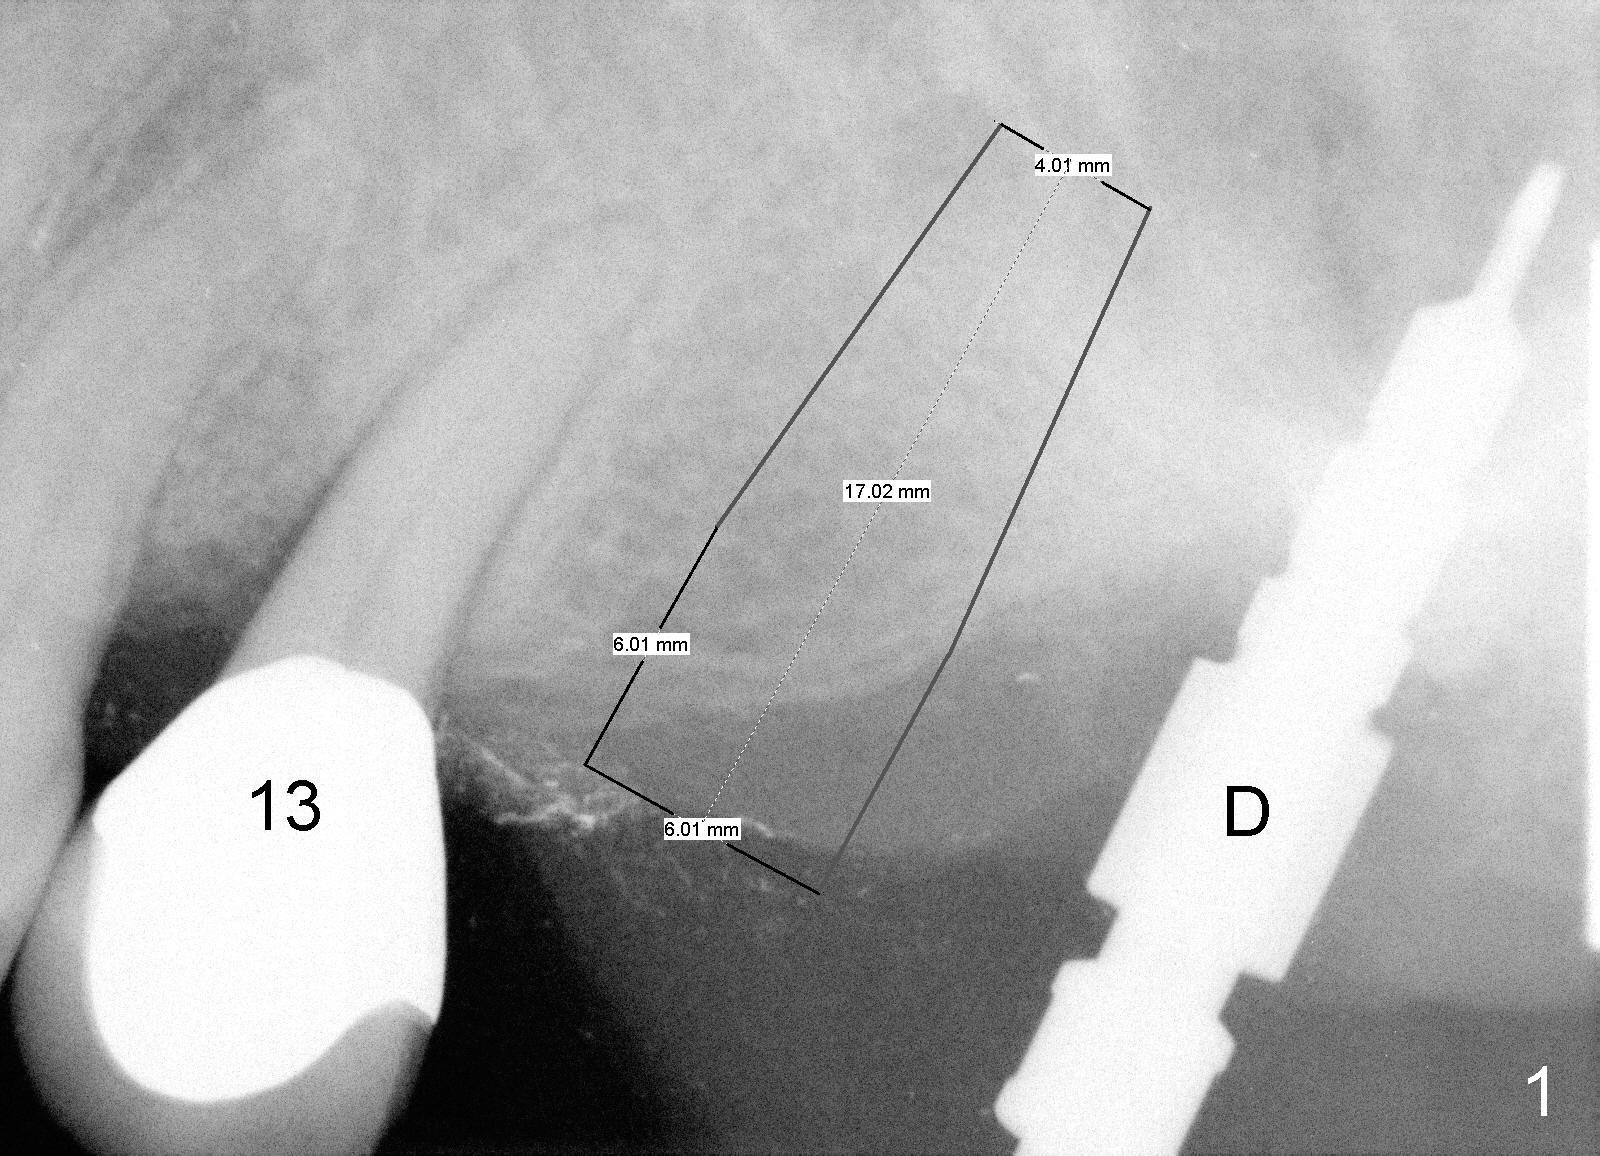

A 58-year-old man used to have a upper left 3-unit bridge. Two months after extraction and immediate implant at the site of the posterior abutment, an implant is planned to be placed at the site of the pontic, #14 (Fig.1). Osteotomy starts with a 1.6 mm pilot drill, followed by bone expanders, parallel to the crown of the tooth #13. The first intraop PA shows that 3.0 mm bone expander is close to the root of the neighboring tooth (Fig.2). No matter what is done to change the trajectory of the osteotomy using expanders according to the crown morphology of the neighboring tooth, the next 3 expander does not improve in parallelism (Fig.3). When a 6x17 mm tap is inserted (Fig.4 T), it is realized that axis of the tap is parallel to the axis of the crown of the neighboring tooth (black line), but not that of the root (red line). It is too late to change the trajectory drastically; a 6x17 mm implant is placed with insertion torque > 60 Ncm (Fig.5). It is best to change the trajectory as early as possible, e.g., after taking the first intraop PA and withdrawing the expander (Fig.6 black area) and as much as possible (red line; starting new osteotomy). It is quite similar to immediate implant. There is no bone loss 2 months postop (Fig.7), 18 months (Fig.8,9) or 34 months (Fig.10)post cementation, in spite of open contact between the crowns (Fig.10 black arrowhead). This is partially due to supragingival margin (Fig.11,12 (immediately pre-cementation)). No bone loss is noted 3 years 5 months post cementation (Fig.13).